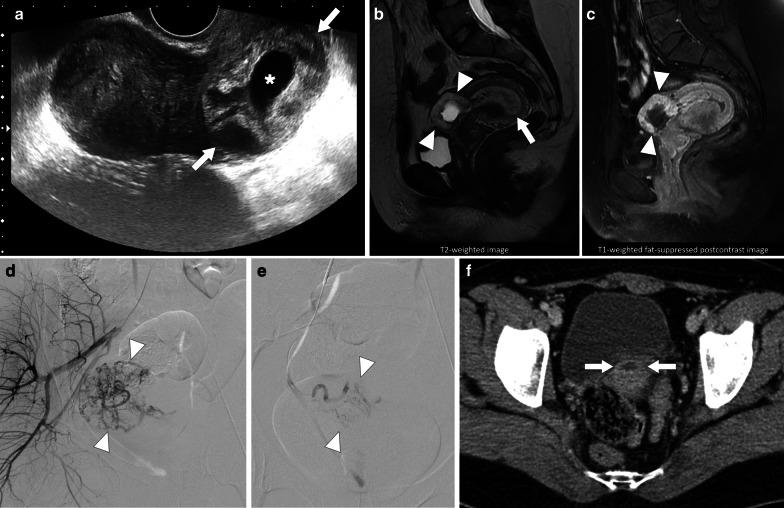

Identifying the deceiver: the non-neoplastic mimickers of genital system neoplasms.

Tumors of the genital system are common and imaging is of crucial importance for their detection and diagnosis. Several non-neoplastic diseases may mimic these tumors and differential diagnosis may be difficult in certain cases. Misdiagnosing non-neoplastic diseases as tumor may prompt unnecessary medical treatment or surgical interventions. In this article, we aimed to present the imaging characteristics of non-neoplastic diseases of the male and female genital systems that may mimic neoplastic processes. Increasing awareness of the imaging specialists to these entities may have a severe positive impact on the management of these patients.